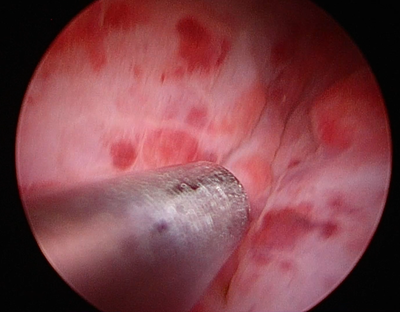

お腹に5-10mm程度の小さな穴をあけてそこから腹腔鏡をお腹の中に挿入します。まずは内視鏡で膀胱を確認してお腹に引っ張ってきてお腹の壁に少し固定します。その小さな傷から膀胱を小切開し、カメラを膀胱内に入れていき内部を観察します。膀胱に開けた穴からカメラや鉗子と呼ばれる器具を入れて膀胱の中で手術をしたり、吸引管と呼ばれる液体を吸い取るための管状の器具をいれます。内視鏡カメラは非常に大きく拡大して内部を観察するために小さな結石や結晶、傷やポリープなどの細かな観察が得意です。

カメラで確認した結石は吸引もしく鉗子による除去を行います。数㎜の小さな結石や結晶は吸引管とよばれる液体を吸引する器具を用いて除去を行います。先端が3-5mm程度ですのでこれ以下の結石はこの器具を用いて摘出します。イメージとしては掃除機を使って小さなホコリを吸い取ってしまような形になります。

吸引管による結石の吸引